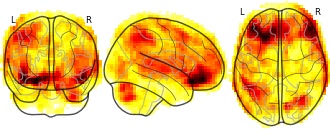

"name": "VBM_HeterogeneityMap",

"description": "Abnormal gray matter in BPD. Brain regions with significant heterogeneity (i.e. between-study variance) in the comparison of patients with BPD and healthy controls. Results are thresholded at at p<.005 & k>20. Note: Results are based on meta-analysis of group comparisons. Note2: Results were updated (see Erratum for this publication)",

"add_date": "2016-01-21T18:23:32.131003+01:00",